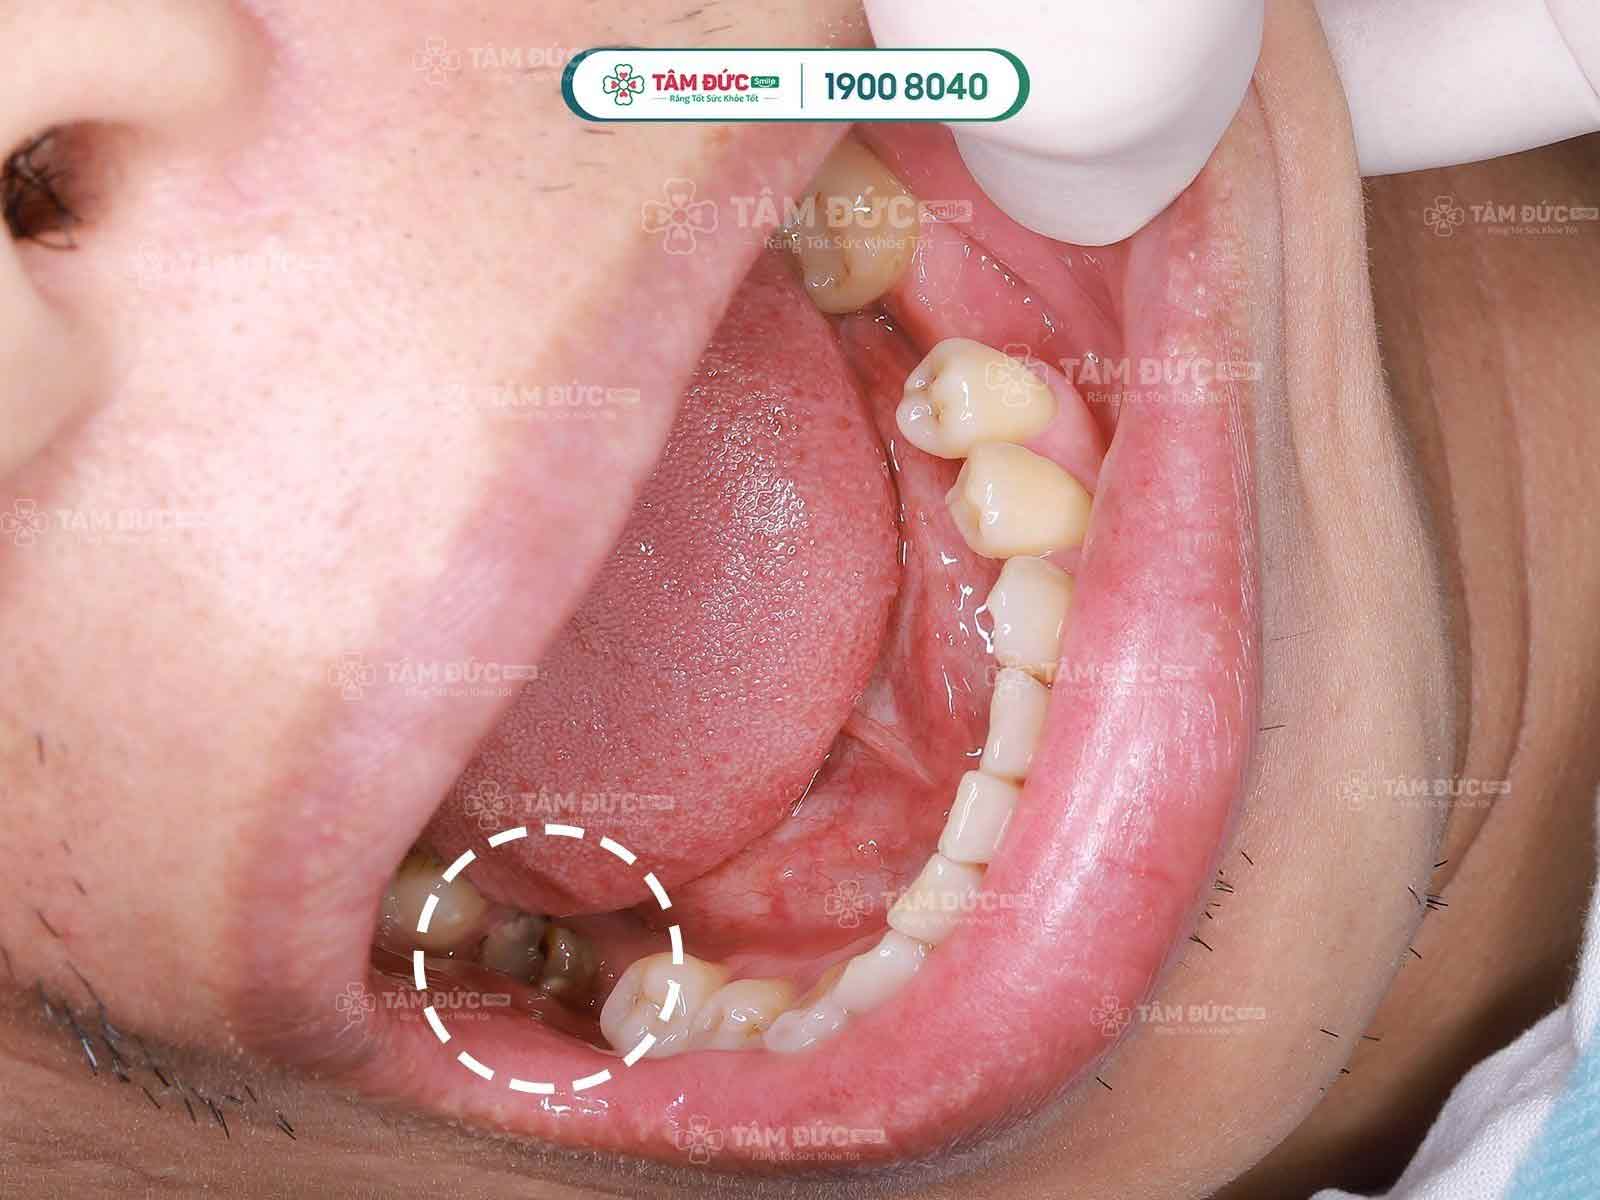

Thường nguyên nhân chính dẫn đến viêm tủy là sâu răng, các mảng bám từ thức ăn lâu ngày không được vệ sinh sẽ hình thành vôi răng, trong vôi răng đó chứa rất nhiều vi khuẩn có khả năng phá hủy, ăn mòn răng của Quý khách xuất hiện tình trạng răng xuất hiện các lỗ đen. Và kéo dài tình trạng này lâu, vi khuẩn sẽ ăn mòn lớp răng vào đến tủy, gây viêm tủy.

Các bệnh nhân sâu ăn vào đến tủy thường sẽ cảm thấy đau nhức răng, ăn nhai khó khăn, ảnh hưởng xấu đến sức khỏe.

Bên cạnh đó, viêm tủy còn có thể bị do chấn thương, răng bị mẻ vỡ nặng cũng ảnh hưởng đến tủy răng. Do trong miệng vẫn tồn tại nhiều vi khuẩn, nên khi răng mẻ vỡ, tủy không được lớp răng bảo vệ thì vi khuẩn rất dễ tấn công, ăn mòn và gây bệnh viêm tủy.

- Răng bị mẻ, vỡ lớn, sâu răng làm lộ tủy gây viêm tủy, nhiễm trùng.